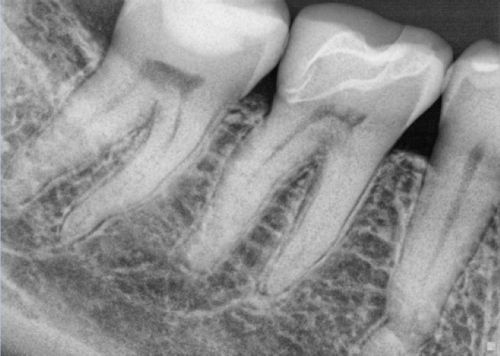

A 54 year old female patient presented to our office last month with a report of acute discomfort localized to tooth #30. An all ceramic restoration was placed three months prior. Since that time, a strong sensitivity to cold had developed in conjunction with slight chewing tenderness. I examined the tooth clinically and confirmed an acute irreversible pulpitis localized to the first molar. After discussing the treatment options we decided to move forward with endodontic therapy. On the pre-operative radiograph the canal system appeared to be rather straight forward with some slight coronal calcification of the mesial canal system. Overall, I was not too concerned with the pre-operative anatomical configuration. Once inside the access, both the mesial lingual and distal buccal canals were located. After troughing with an ultrasonic tip under high magnification, I could see the delineation of reparative dentin over the orifice of the MB canal. A slight stick with a 6 C plus file was noted along the lingual wall of the distal canal; however a separate orifice could not be visualized under the microscope.

Pre Operative Radiograph